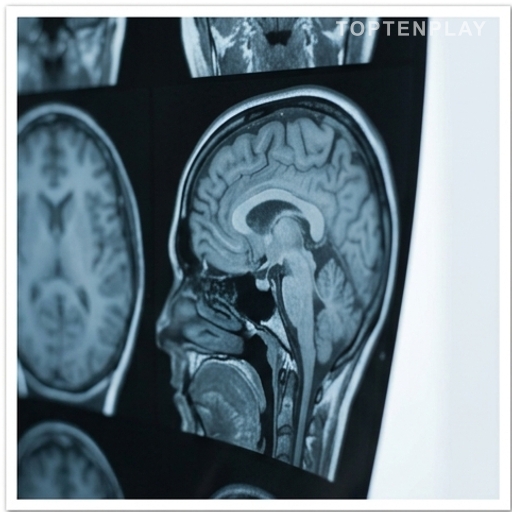

Depuis plusieurs mois, les spéculations allaient bon train sur l’état de santé de Laurence Boccolini. L’animatrice a décidé de briser le silence : elle souffre d’un paragangliome intra-tympanique, une tumeur rare de l’oreille moyenne. Si elle tient à préciser qu’il ne s’agit pas d’un cancer, cette pathologie fait peser sur elle des risques sérieux de paralysie faciale et d’atteinte à la voix.

Invitée dans l’émission Le Jet de Luxe, Laurence Boccolini a choisi de clarifier publiquement la nature de sa maladie. « Ce n’est pas un cancer. Ce n’est pas une tumeur qui va métastaser »,…